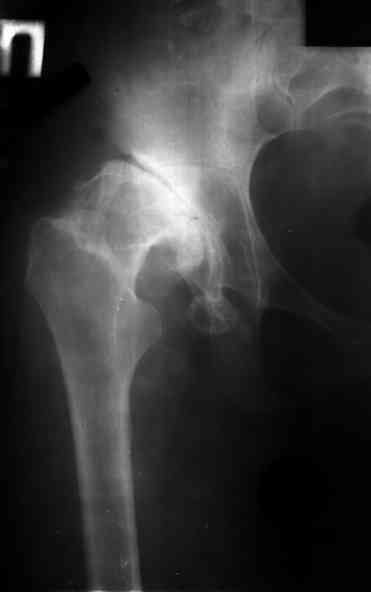

Ув. коллеги, женщина, 37 лет, имеет диспластический коксартроз. Сомневается в положительном результате от эндопротезирования, но хочет оперироваться. Что порекомендуете? С ув. Sergey A. Melashenko ул. Кирова 88-А, г. Приморск, Запорожская обл., 72100, Украина

Оперироваться. Альтернативы нет. Надо делать обе ноги, поочередно с реконструкцией крыш для последующей удобной ревизии. Ножки бесцементные.

Остальное дело техники. С ув. А Рыков. Хабаровск. Мы бы взялись.

Сергей. Операция первичного эндопротезирования предусматривает у данной больной (я бы сделал так) - 1. Доступ с хорошим обзором впадины (или задний

или с пересечением б.вертела) - затем установку тазового компонента с одномоментной пластикой крыши вертлужной впадины из утилизируемой головки

(если получится бесцементная чаша - это лучше, но не факт - вероятно будет моделирующее кольцо с цементируемой чашей - внимание к "версии" чаши) -

затем классическая бесцементная ножка. Справа будет попроще. Слева рассчет после установки правого сустава. Может потребоваться двухэтапное

протезирование. При отсутствии проблем с финансировании - отправьта в Харьков - Киев - Донецк. С уважением. А Рыков.

1. при таком анатомическом варианте корригирующие остеотомии явно проигрывают тотальному эндопротезированию.

2. первым этапом оперируем сторону с преобладающим болевым.

3. справа может быть будет достаточно структурного аутотрансплантата, но вариант с кольцом надо иметь в виду; слева использовал бы армирующую конструкцию (плохая надацетабулярная кость - проблемное приживление трансплантата).

4. вероятность осложнений выше, чем в банальной ситуации, правильно дама беспокоится, лучше делать операцию там, где это на потоке. Если ближе не найдется, присылайте.

Сергей, Курганский Цент Илизарова и ортопедическое отделение №10 может принять вашу пациентку и выполнить ей тотальное эндопротезирование.

Опыт протезирования диспластических коксартрозов достаточный.

Видимо, придется использовать цементную впадину и бесцементную ножку. Хотя кость во впадине есть, мможно выполнить и бесцементный вариант фиксации. Думаю получится.